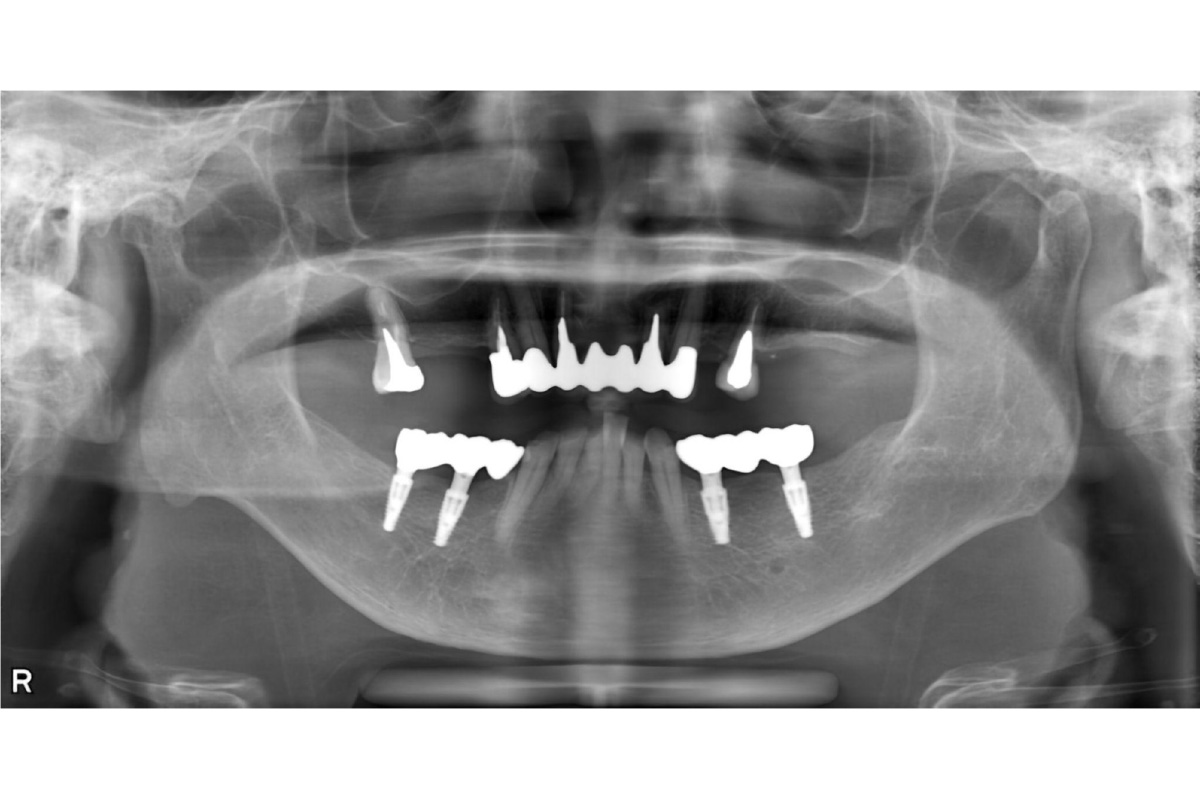

治療後